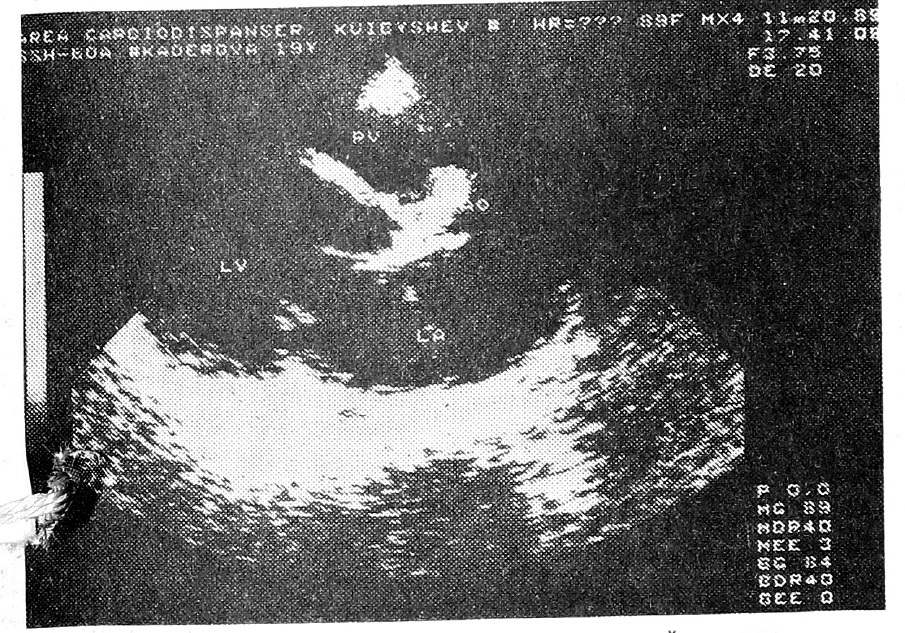

ЭХОКГ: конечный диастолический объем — 345 см3, ударный объем — 73 см3, фракция выброса—21%, дилатация всех полостей сердца с выраженным снижением сократительной функции, наличие перикардиального выпота (рис. 1).

Рис. 1. ЭХОКГ: дилатация всех полостей сердца.